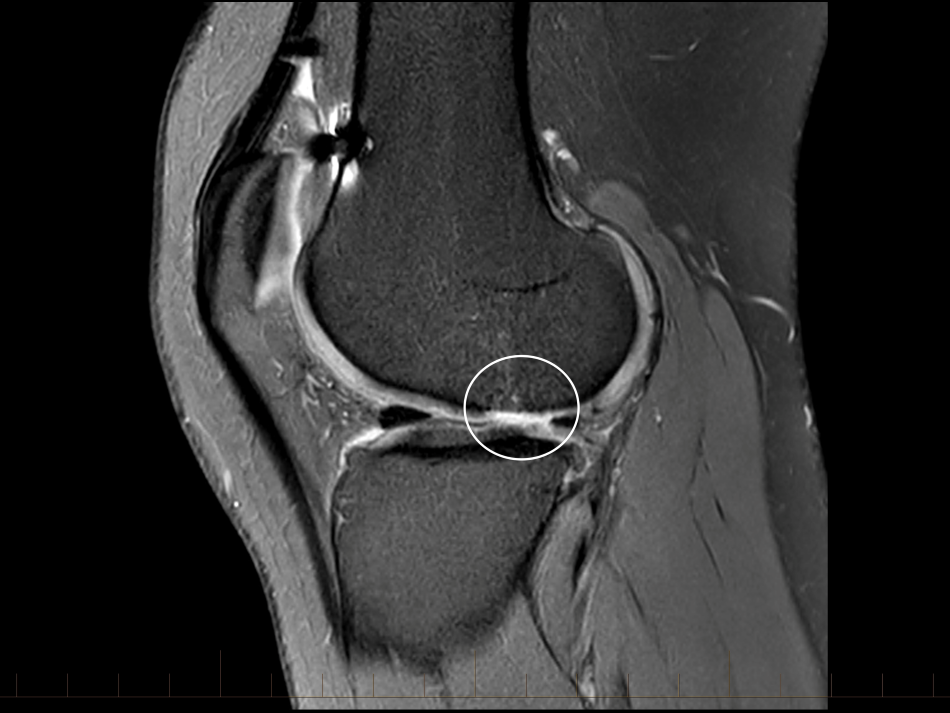

The ACL graft is ruptured with a loss of the normal ACL contour and signal. There is a focal are of full-thickness cartilage loss on the posterior, weight-bearing portion of the lateral femoral condyle. This measure approximately 15 x 10mm. There is also thinning and irregularity of the articular cartilage involving the posterior aspect of the lateral tibial plateau with a small area of full thickness cartilage loss and subchondral reactive change. These chondral changes were not present at the time of her first surgery. There appears to have been trimming of the mid and posterior thirds of both menisci. These meniscal remnants are small and irregular.